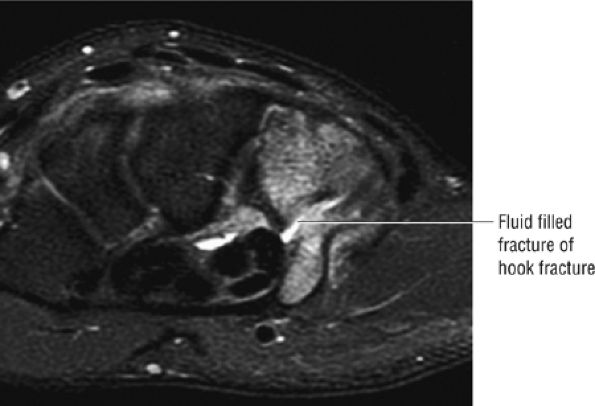

FIGURE 10.1 ● A 3D fast spoiled GRASS (FSPGR) with intra-articular contrast injected into the radiocarpal compartment. The torn lunotriquetral ligament (straight arrow) allows extension of contrast into the midcarpal compartment and the torn radial attachment of the TFC (curved arrow) directs contrast into the distal radioulnar joint. Note the superior trabecular bone detail on this image (coronal image; TR, 40.4 msec; TE, 14.5 msec; FOV, 4 cm; slice thickness, 2.0 mm; matrix, 512 × 256; flip angle, 30°).